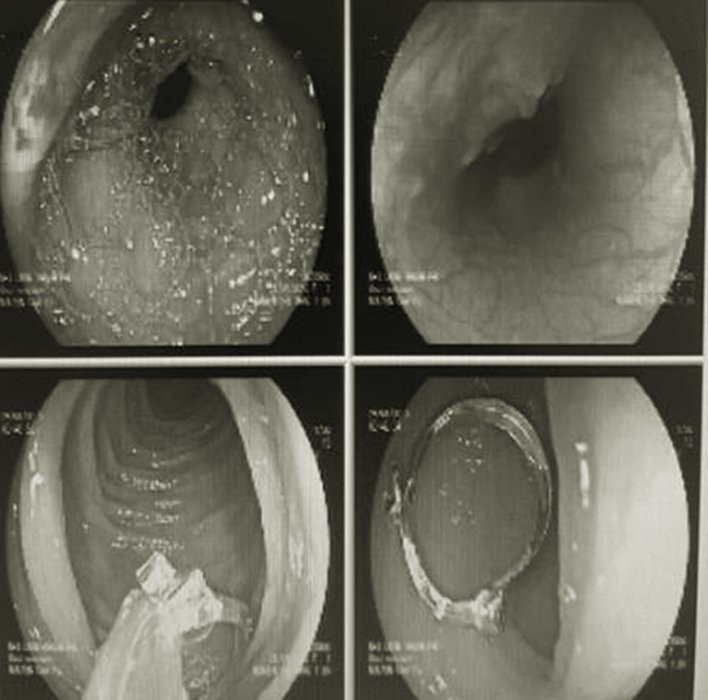

Hình ảnh phim chụp dị vật là chiếc khuyên tai trong thực quản của bệnh nhi 12 tháng tuổi ở TP.HCM. (Ảnh: BVCC)

Qua phim chụp X-quang, các bác sĩ phát hiện dị vật trong thực quản của bệnh nhi, nhưng không can thiệp được nên đề nghị chuyển ngay bé đến Bệnh Viện Nhi Đồng Thành Phố. Tại đây, quá trình thăm khám và làm các xét nghiệm cho thấy dị vật hình chiếc khuyên tai nằm trong hầu họng đã di chuyển xuống dạ dày bệnh nhi.

Bệnh nhi được gây mê, nội soi gắp dị vật (khuyên tai) ra khỏi thực quản.

Theo bác sĩ Nguyễn Cẩm Tú, trưởng khoa Tiêu hoá, do dị vật là chiếc khuyên tai có một đầu nhọn nên có nguy cơ cao sẽ gây trầy rách niêm mạc đường ruột khi bác sĩ làm thủ thuật lấy dị vật. Nhưng khi kiểm tra lòng thực quản và dạ dày của bệnh nhi chỉ tổn thương ít niêm mạc.